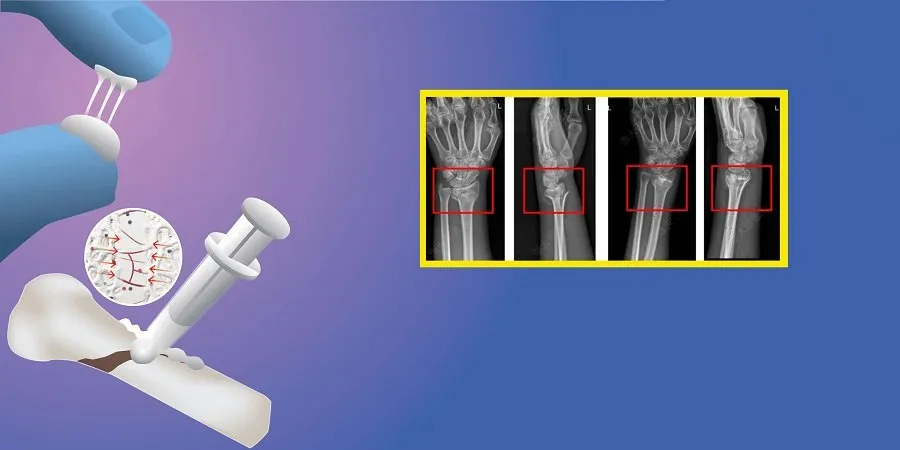

પરીક્ષણ અને સફળતા

બૉન ગ્લુનું અત્યાર સુધીમાં 150થી વધુ દર્દીઓ પર પરીક્ષણ કરવામાં આવ્યું છે. લેબ ટેસ્ટમાં તે સાબિત થયું કે ગ્લુ 200 કિલો સુધીનું વજન સહન કરી શકે છે. ટેસ્ટ દરમિયાન હાડકાંને જોડવામાં આ ગ્લુ માત્ર 2-3 મિનિટનો સમય લે છે. ત્યારબાદ છ મહિના સુધી તેના પરિણામોનું નિરીક્ષણ કરવામાં આવ્યું, જેમાં જોવા મળ્યું કે ગ્લુ આપોઆપ સુકાઈ ગયો અને શરીરના કોષો સાથે સંપૂર્ણપણે ભળી ગયો.